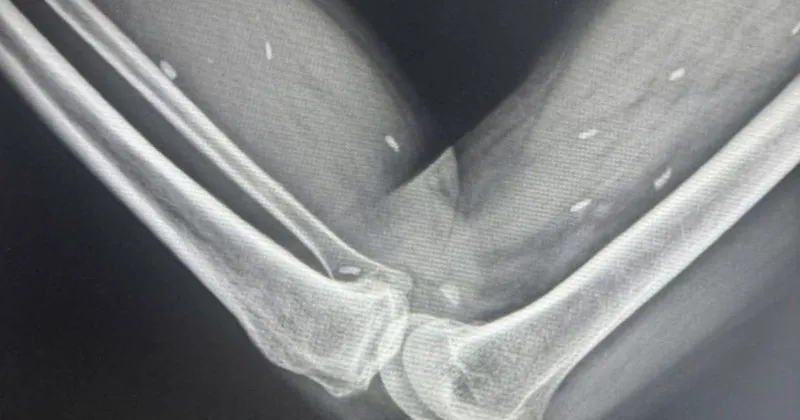

Qua chụp X-quang, các bác sĩ phát hiện nhiều kén sán kích thước như hạt gạo nằm rải rác ở các mô vùng đùi và cẳng chân bệnh nhân. Khi khai thác tiền sử dịch tễ, người bệnh cho biết có thói quen ăn rau sống. Sau đó, bệnh nhân đã được chuyển lên tuyến trên để tiếp tục điều trị.